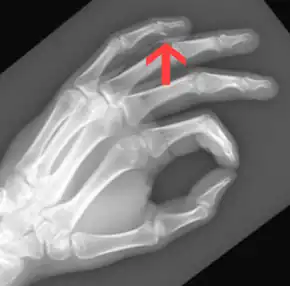

It typically occurs when one athlete grabs another's jersey as they are pulling away.[1] The underlying mechanism involves the forced straightening of a flexed finger tip.[1] Diagnosis is often by examination, supported by X-ray or ultrasound.[1] It maybe an avulsion fracture (when a piece of bone is torn off) or an isolated tendon injury.[3][1]

A jersey finger is a traumatic rupture of the flexor digitorum profundus (FDP) tendon at its point of attachment to the distal phalanx.[8] This injury often occurs in American football when a player grabs another player's jersey with the tips of one or more fingers while that player is pulling or running away.[9] The force of this action hyperextends the tip of the finger at the DIP joint while the proximal portion of the finger is flexed. This action can partially or completely rupture the FDP tendon at or near its attachment point on the distal phalanx. Sometimes, the force is great enough to pull off or avulse a piece of phalangeal bone to which the tendon can remain attached.[10] Although it is a common football injury, this injury can occur during other sports or activities as well.